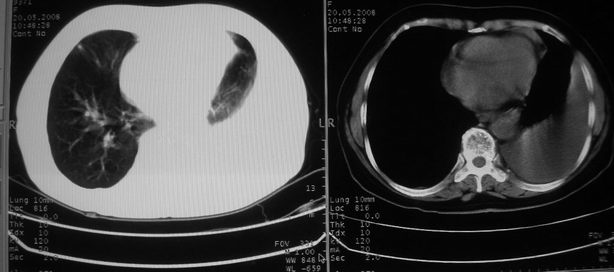

以下是引用w_jianhua在2008-5-22 12:59:00的发言:[br]1.左肺上叶肺癌并左侧胸腔积液可能性大。2不除外支气管内膜结核并包裹性胸腔积液,建议支气管镜检3.左肺下叶肺大泡,肺气肿